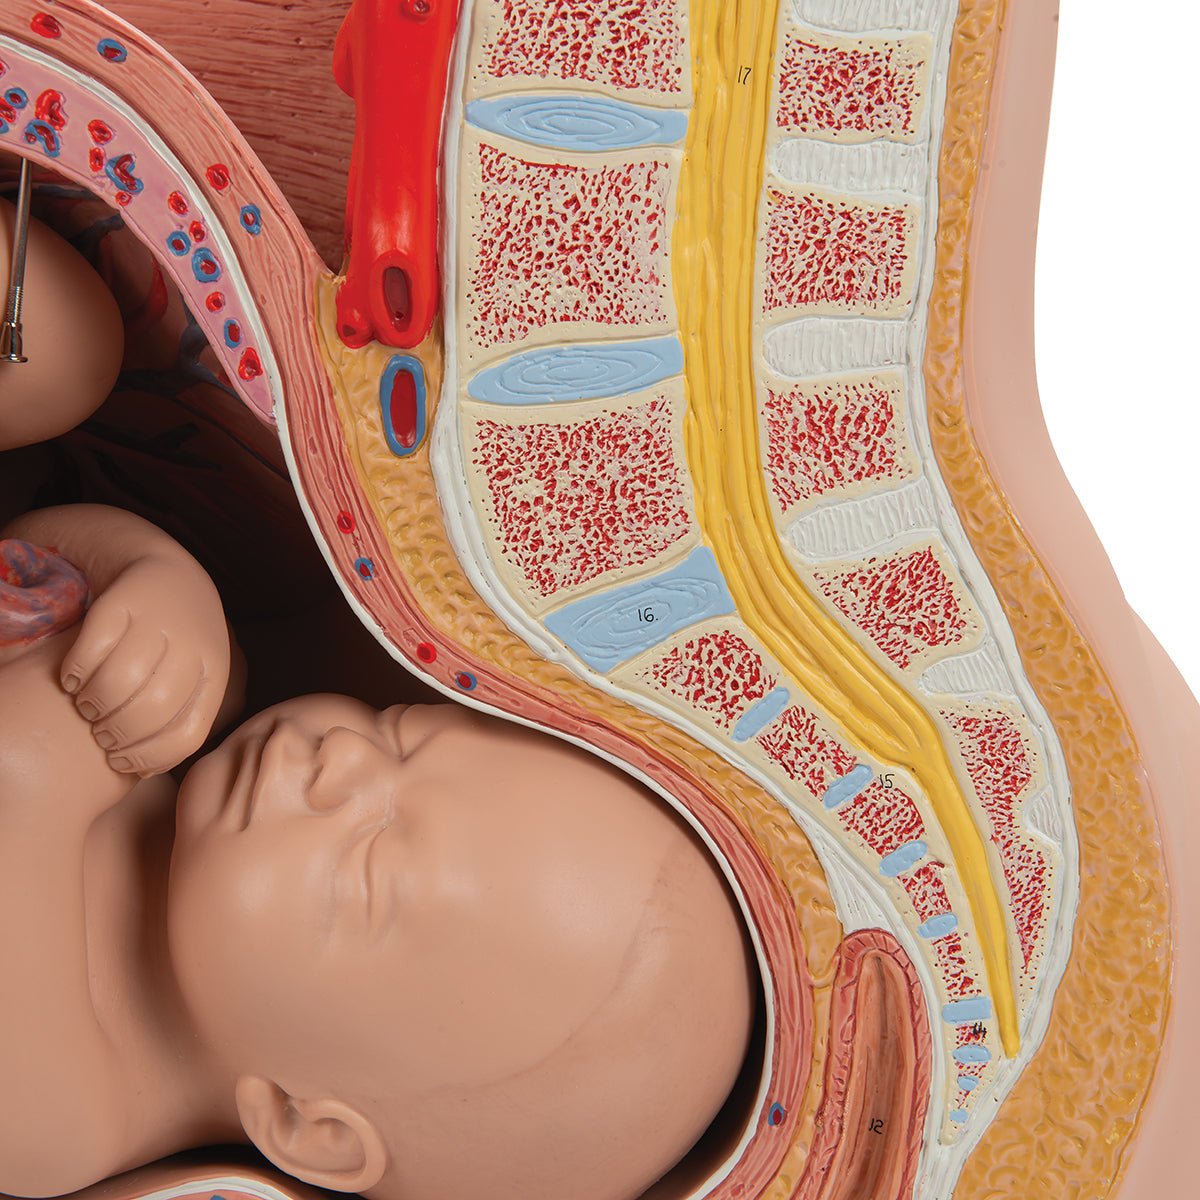

Selling anatomical models is the mainstay of eAnatomi, although we also spend a lot of resources developing our own anatomical materials such as posters. Anatomical models are used for various purposes and can show both defined tissues, organs and organ systems. Are you looking for a simple model of bone tissue or perhaps an advanced torso model based on MRI technology, you can find it all at eanatomi.com.